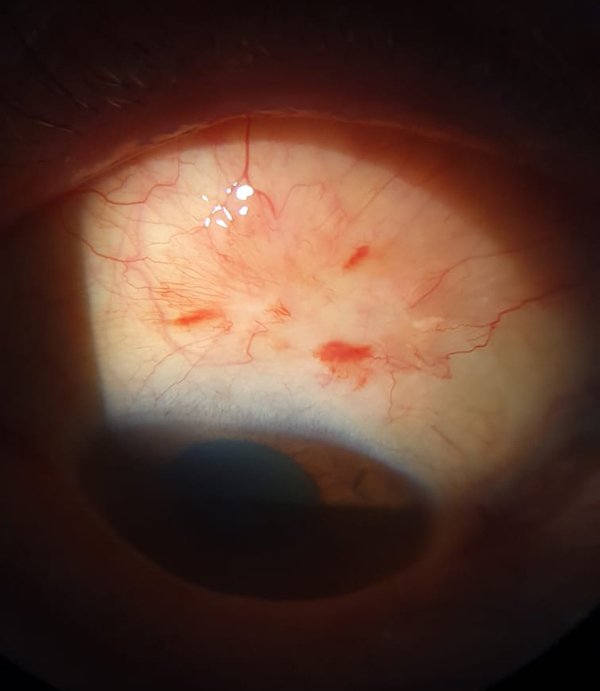

A pesar del tratamiento tópico durante 4 semanas, no se logró disminución del tamaño de granuloma por lo que se hizo intervención quirúrgica para exéresis de lesión granulomatosa y análisis anatomopatológico. El reporte anatomopatológico mostró tejido de granulación inflamatoria que confirmó el diagnóstico de granuloma piógeno conjuntival en sitio de obtención de injerto. Se continuó el tratamiento con prednisolona oftálmica tópica 1% durante 2 semanas. En los controles sucesivos presentaba reepitelización adecuada de área quirúrgica temporal superior, por lo que se anexó al tratamiento: gatifloxacina 0,3% y dexametasona 0,1% tres veces por día durante 2 semanas, observándose finalmente curación del sitio quirúrgico (fig. 2). El paciente mantuvo un seguimiento durante 6 meses y no se observaron recidivas ni complicaciones posteriores —ni del granuloma ni del pterigión— durante esos meses.

Figura 2. Cicatrización conjuntival luego de la escisión quirúrgica del granuloma.